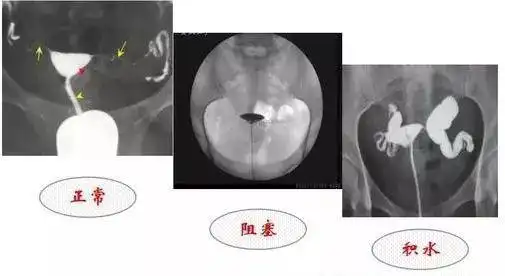

如何看懂输卵管堵塞,粘连,积水造影片子!

教你如何看懂输卵管堵塞粘连积水造影片子

输卵管造影片的解读你理解对了吗